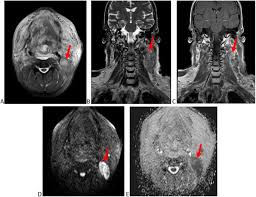

Cervical Lymph Node Enlargement As The Initial Manifestation Of Rectal Cancer Bmc Gastroenterology Full Text

Cervical Lymph Node Enlargement As The Initial Manifestation Of Rectal Cancer Bmc Gastroenterology Full Text from media.springernature.com